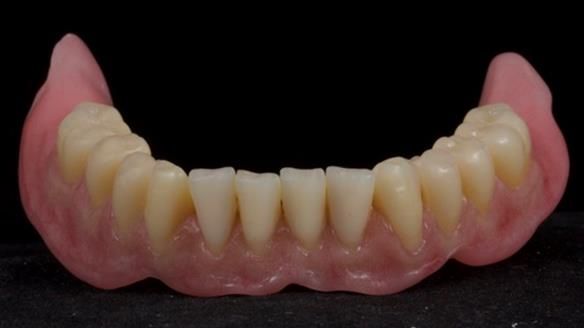

The detailed clinical situation and treatment process are outlined below, with clinical work provided by me and technical work by Rowan Garstang. The treatment spanned 12 months, involving removing 5 upper anterior teeth, adding to an existing upper RPD, followed by creating and fitting metal based complete dentures.